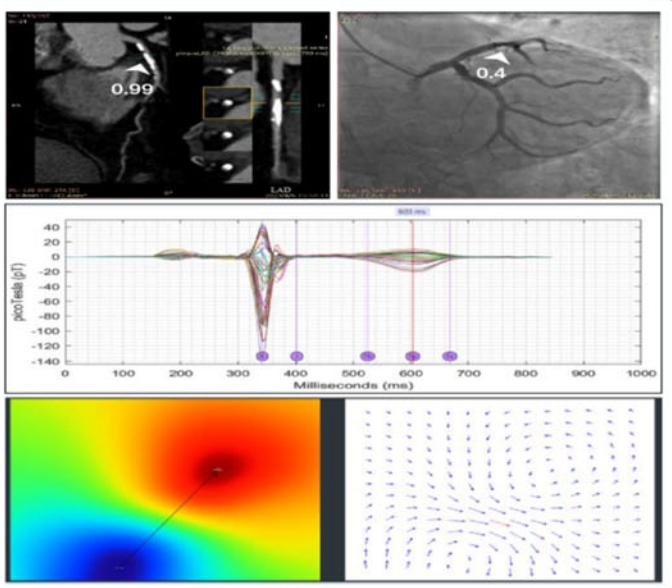

图3 一例高钙化积分下MCG与CCTA诊断性能比较的病例分享

研究结果显示,MCG诊断CAD的AUC为0.80,敏感度为74.64%,特异度为84.91%。进一步,根据冠脉钙化积分(CACS)分为<100、100-400和≥400三个亚组。随着CACS的增加,CCTA的诊断特异度显著降低(分别为78.57%、24.13%、17.46%),而MCG的诊断特异度则保持稳定(分别为92.86%、86.21%、82.54%)。当CACS≥400时,MCG及联合诊断模型的诊断准确性显著优于CCTA(77.22% vs 67.22% vs 58.89%),AUC分别为0.78、0.71和0.49。